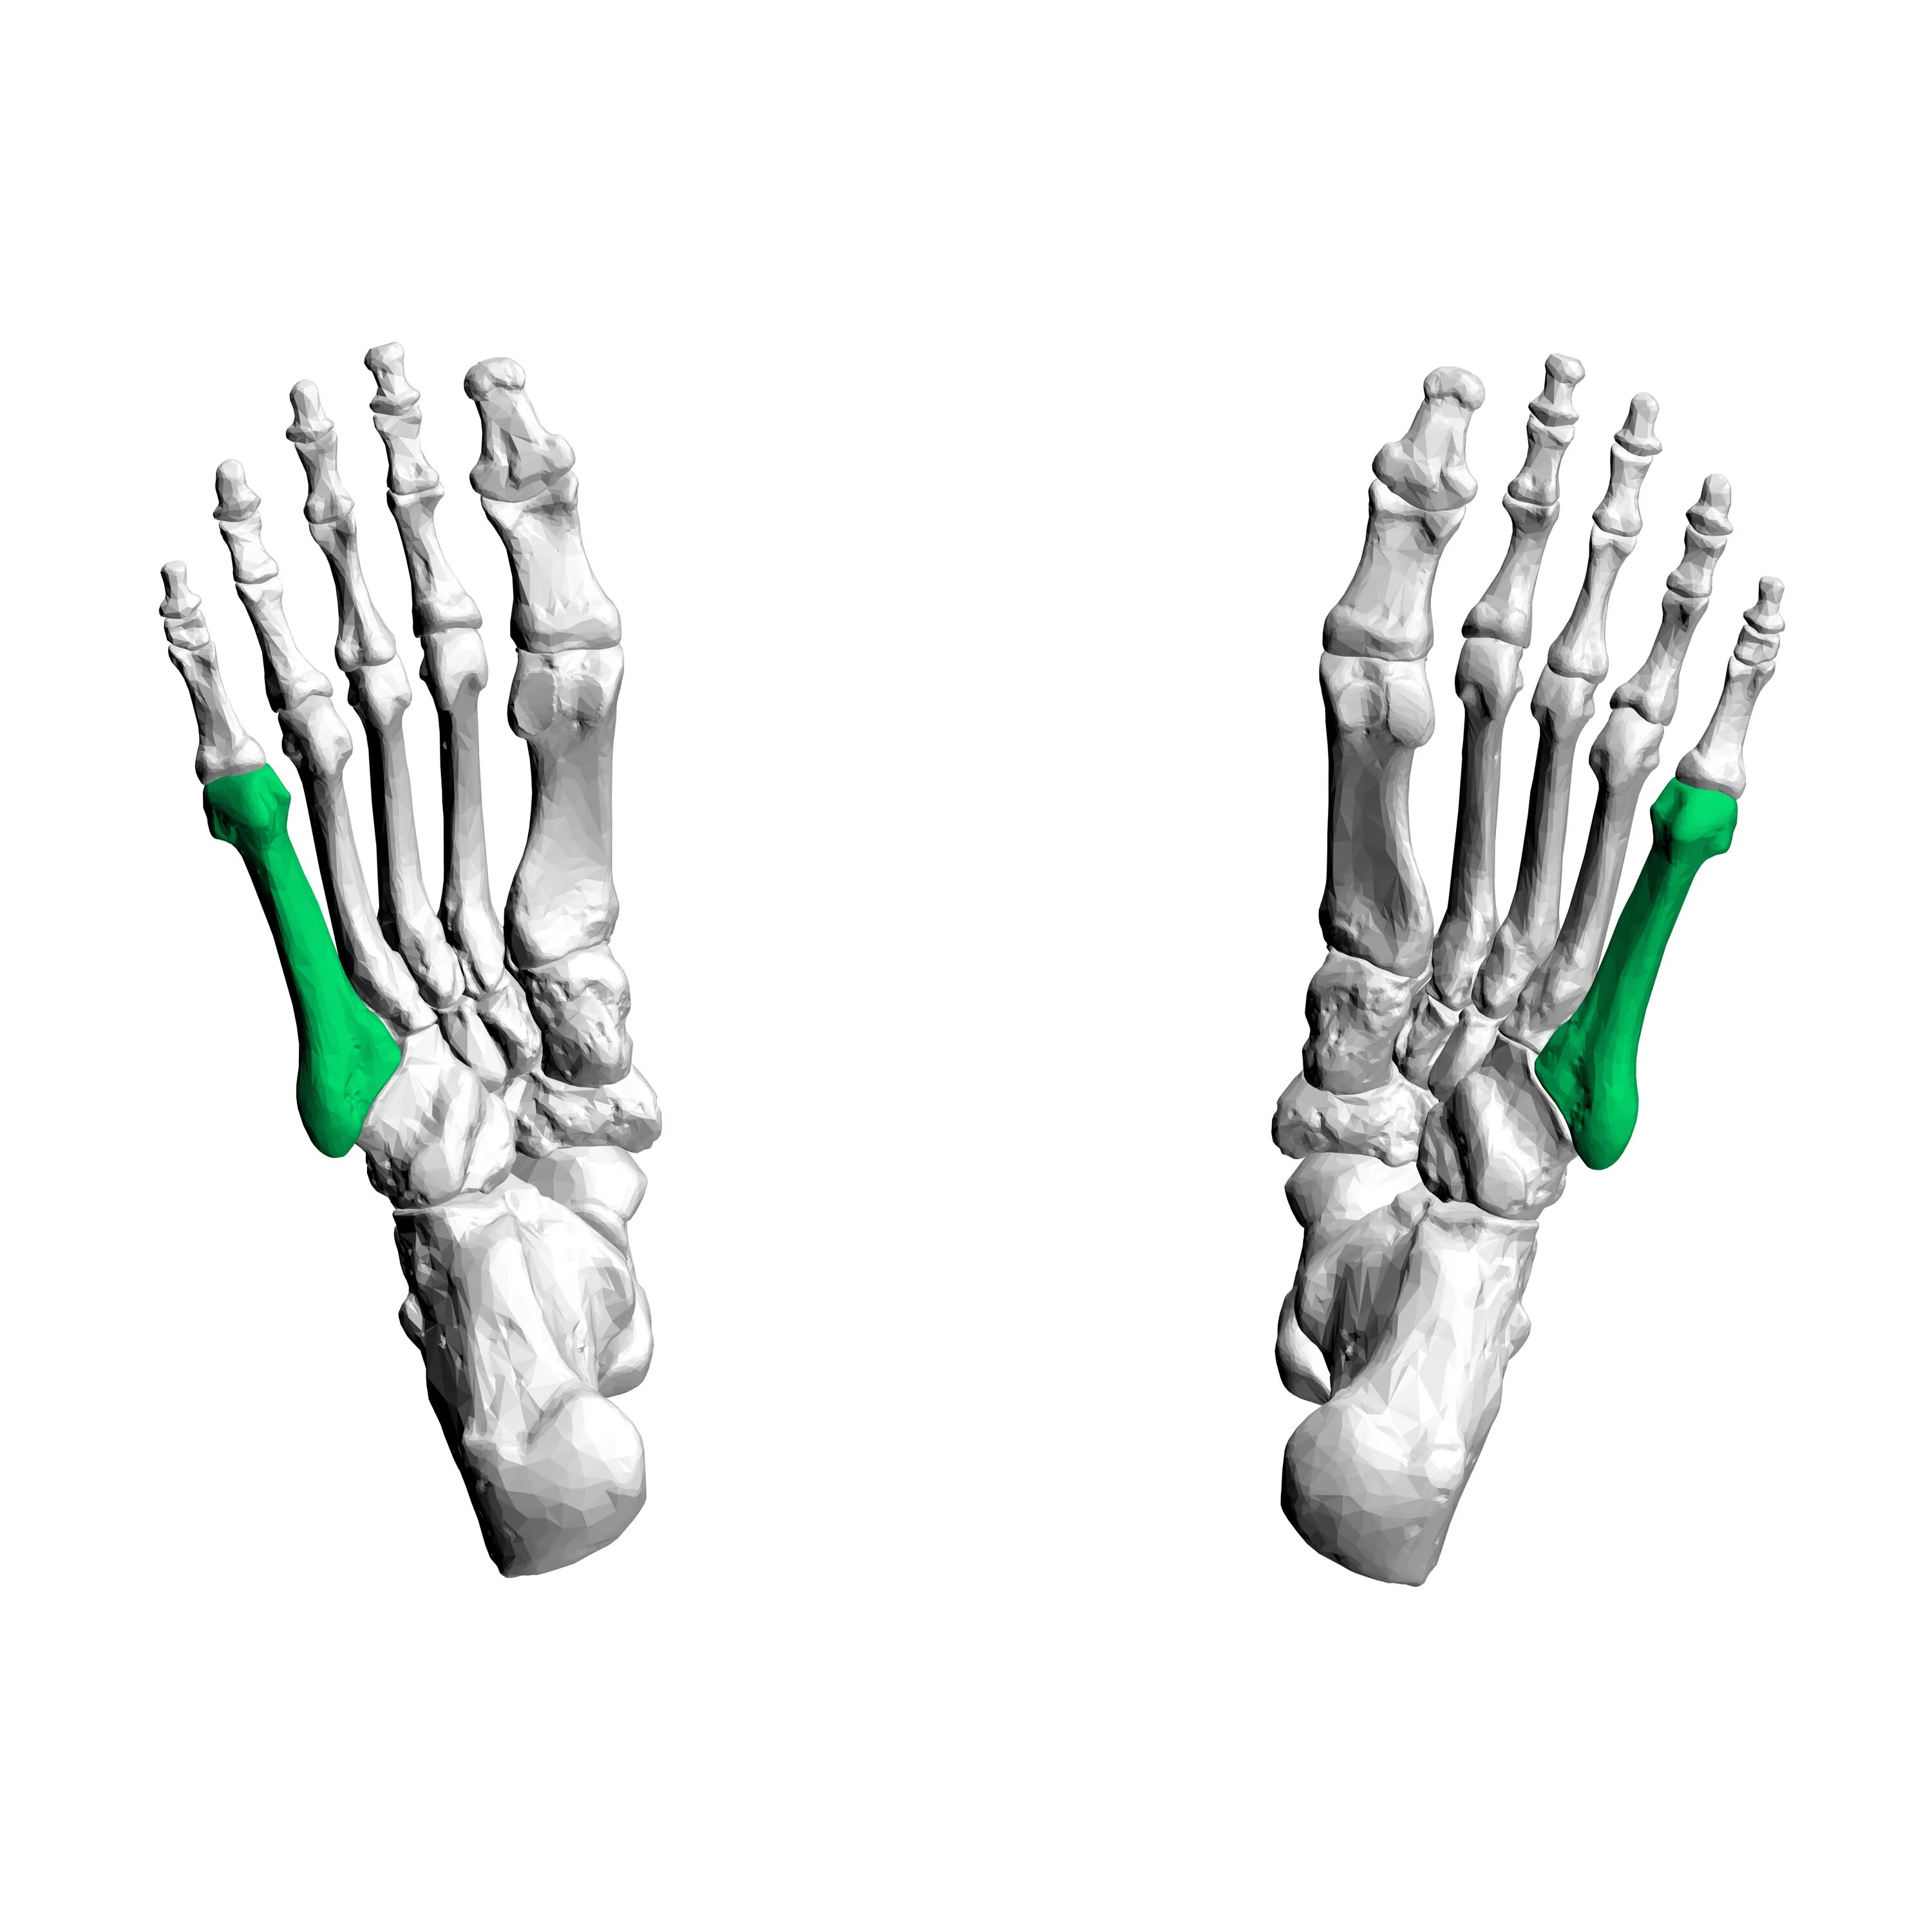

Пяточная остеотомия